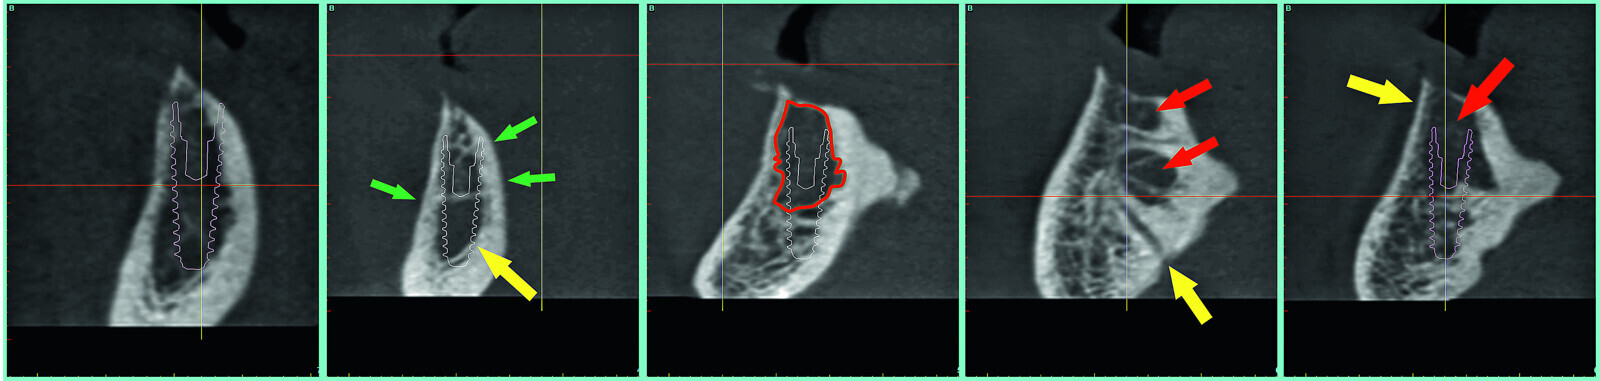

Fig. 8: The need for bone reduction to flatten the ridge for implant placement (red arrows).

Fig. 9: The axial and 3-D reconstructed views revealing the IAN’s, and four proposed implants in the symphysis.

Fig. 10: The cross-sectional slices revealing ‘hollow’ areas in the symphysis.

Fig. 11a: The ‘clipping’ view with simulated implants reveals ‘hollow’ areas in the symphysis.

Fig. 11b: The ‘clipping’ view with simulated implants reveals ‘hollow’ areas in the symphysis.